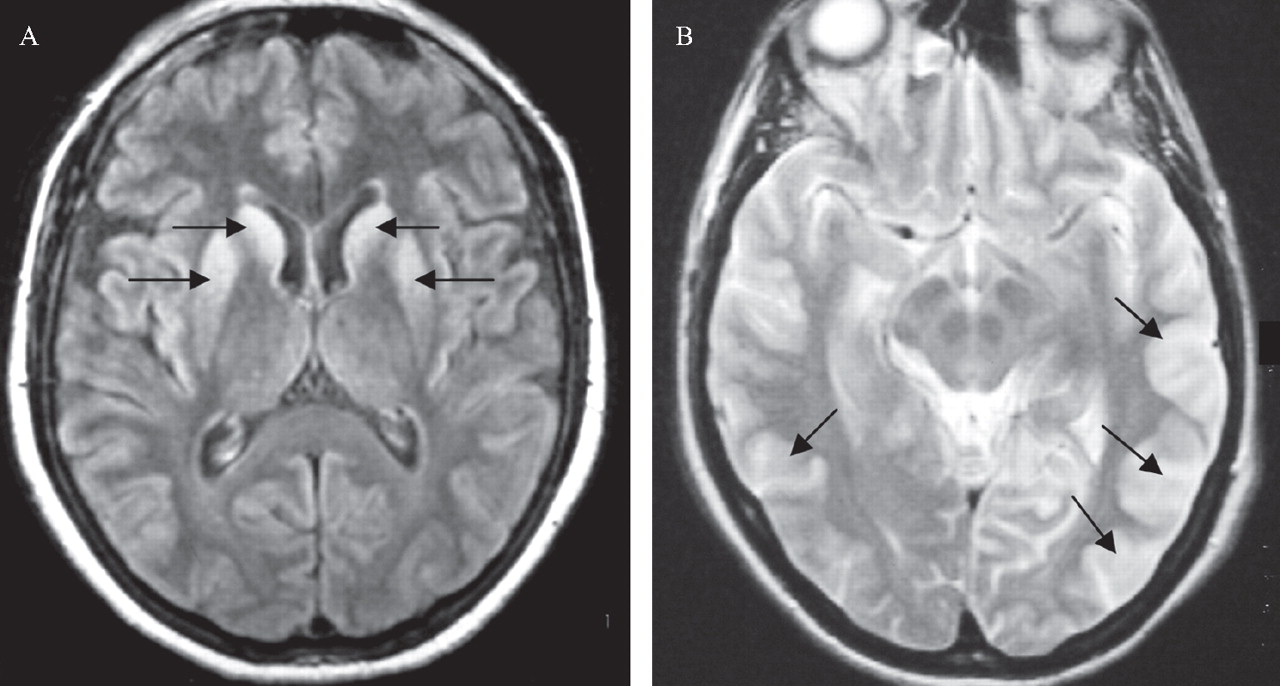

Brain in CreutzfeldtJakob disease, MRI Stock Image C023/9784 Creutzfeldt-Jakob Disease Transmissible Spongiform Encephalopathy Cjd is a degenerative brain disease, meaning it causes damage to your brain that. It is one of a group of diseases called. Transmissible spongiform encephalopathies (tses), also known as prion diseases, are a group of rare degenerative brain. Cjd is classified as a transmissible spongiform encephalopathy (tse) along with other prion diseases that occur in. This condition belongs to. Creutzfeldt-Jakob Disease Transmissible Spongiform Encephalopathy.